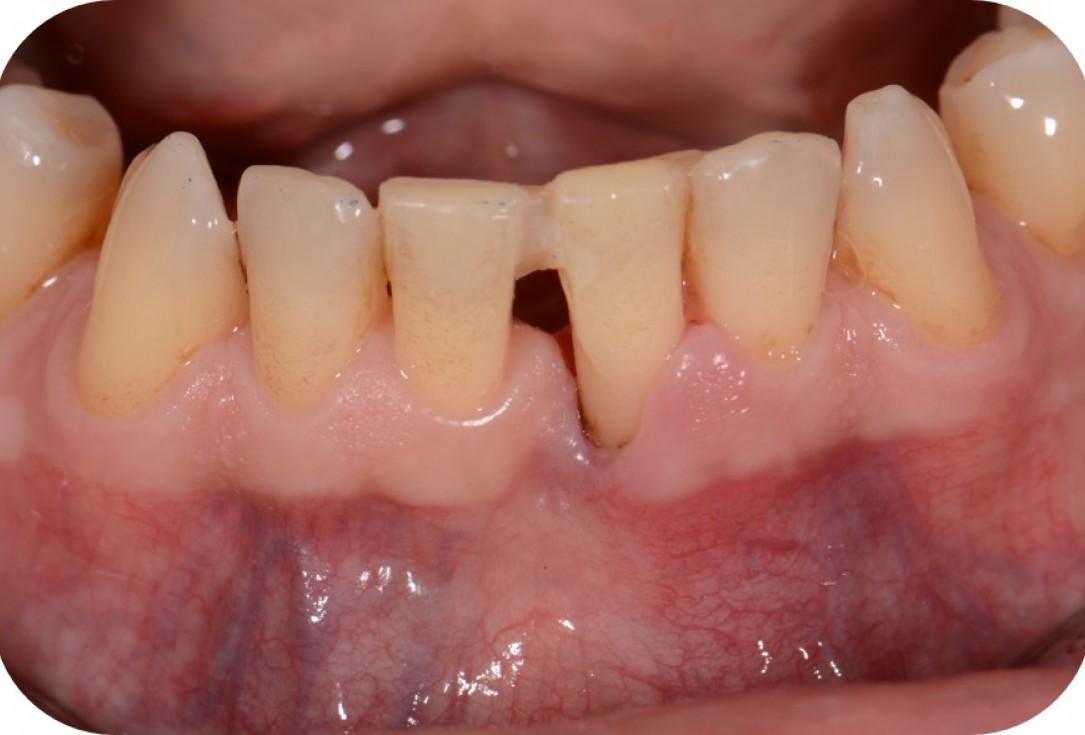

01/12 - Pre-operative clinical situation.Two-wall intrabony defect treated using cerabone® and Straumann® Emdogain® - Dr. D. Rakasevic & Prof. Dr. S. Jankovic